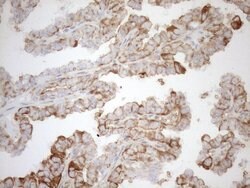

| Immunohistochemistry (Paraffin), Western Blot | |